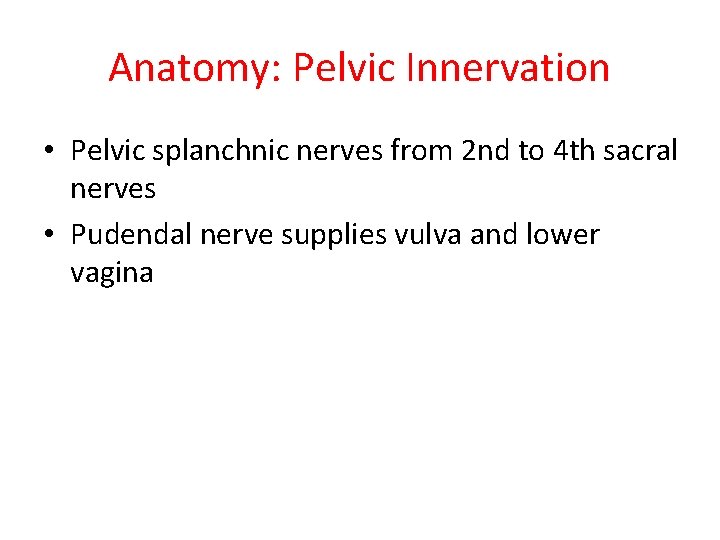

Anatomy: Pelvic Innervation • Pelvic splanchnic nerves from 2 nd to 4 th sacral nerves • Pudendal nerve supplies vulva and lower vagina

• Vulva blood supply comes from a terminal branch of the a. iliaca interna - a. pudenda interna • N. pudendus